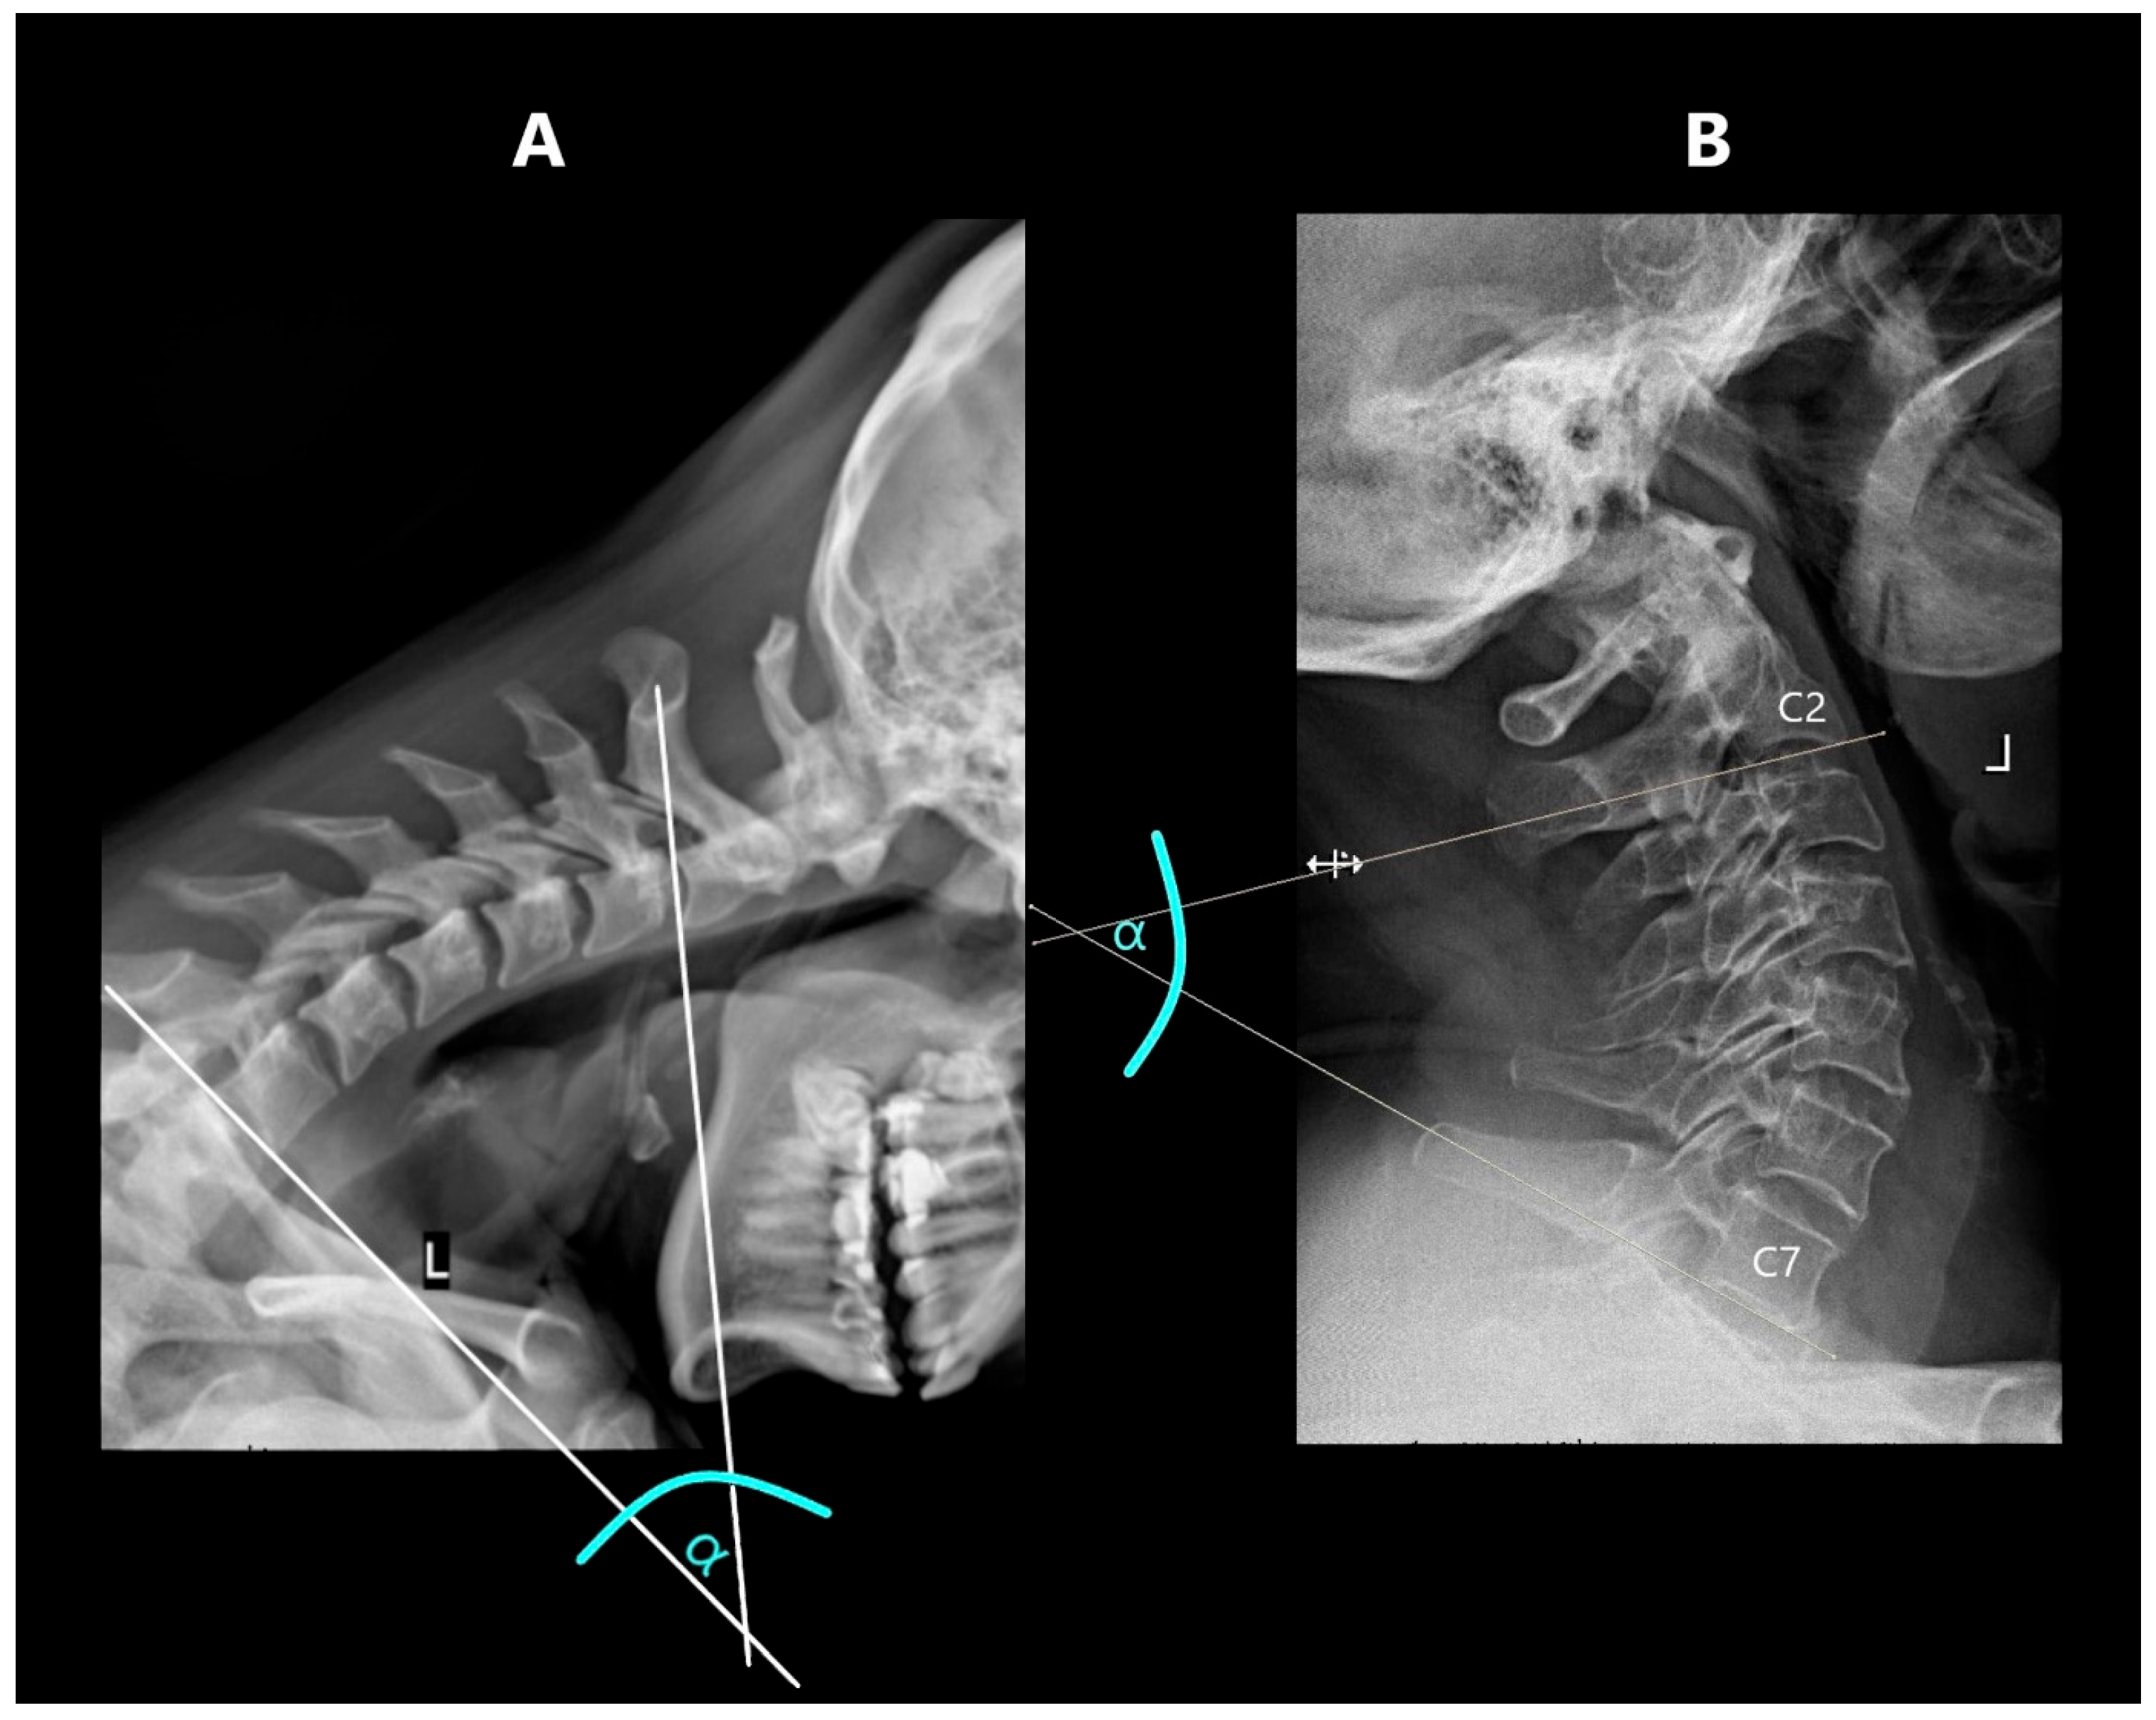

The cervical segmental curvature index was defined as the difference between the heights in the anterior and posterior parts of a particular intervertebral space in relation to the height of the lower vertebral body, which was measured in its posterior part (Figure 4). In flexion, the difference between the sizes of the posterior and anterior parts was counted, while in extension, the size of the posterior part was subtracted from the size of the anterior part [6].

The cervical segmental curvature index was also measured for the entire C2–C7 spine by summing the indices of the individual constituent units (C2–C3, C3–C4, C4–C5, C5–C6 and C6–C7) in the flexion and extension position: total curvature in extension (tCIE); total curvature in flexion (tCIF).

Figure 4. Measurement of curvature in extension (CIE) and in flexion (CIF). (A)—CIE, (B)—CIF.